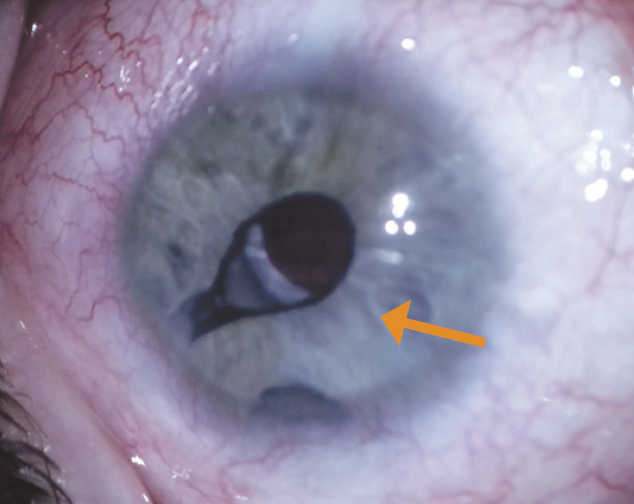

- Retraction of the iris to the tube, with a change in the pupil shape in three eyes (4.5%) (Fig. 6).

Fig. 6. Retraction of the iris to the tube (shown by the arrow) / Рис. 6. Ретракция радужки к трубке (показана стрелкой)